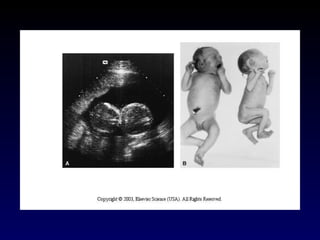

Diagrams illustrating how dizygotic (DZ) twins develop from two zygotes. The relations of the fetal membranes and placentas are shown for instances in which A, the blastocysts implant separately, and B, the blastocysts implant close together. In both cases there are two amnions and two chorions. The placentas are usually fused when they implant close together.

Diagrams illustrating how about 35% of monozygotic (MZ) twins develop from one zygote. Separation of the blastomeres may occur anywhere from the two-cell stage to the morula stage, producing two identical blastocysts. Each embryo subsequently develops its own amniotic and chorionic sacs. The placentas may be separate or fused. In 25% of cases there is a single placenta resulting from secondary fusion and in 10% of cases there are two placentas. In the latter cases, examination of the placenta would suggest that they were dizygotic (DZ) twins. This explains why some MZ twins are wrongly stated to be DZ twins at birth.

Diagrams illustrating how about 65% of monozygotic (MZ) twins develop from one zygote by division of the embryoblast (inner cell mass) of the blastocyst. These twins always have separate amnions, a single chorionic sac, and a common placenta. If there is anastomosis of the placental vessels, one twin may receive most of the nutrition from the placenta. Inset, monozygotic twins, 17-weeks gestation. (Courtesy of Dr. Robert Jordan.).

Diagrams illustrating how some monozygotic (MZ) twins develop. This method of development is very uncommon. Division of the embryonic disc results in two embryos within one amniotic sac. A, Complete division of the embryonic disc gives rise to twins. Such twins rarely survive because their umbilical cords are often so entangled that interruption of the blood supply to the fetuses occurs. B and C, Incomplete division of the disc results in various types of conjoined twins.

Diagrams illustrating howabout 65% of monozygotic (MZ) twins develop from one zygote by division of the embryoblast (inner cell mass) of the blastocyst. These twins always have separate amnions, a single chorionic sac, and a common placenta. If there is anastomosis of the placental vessels, one twin may receive most of the nutrition from the placenta. Inset, monozygotic twins, 17-weeks gestation. (Courtesy of Dr. Robert Jordan.).